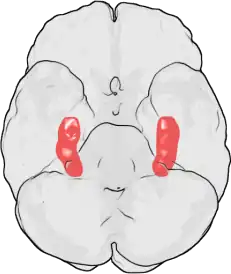

Hipocampo é uma estrutura localizada nos lobos temporais do cérebro humano, considerada a principal sede da memória e importante componente do sistema límbico. Além disso é relacionado com a navegação espacial.[1]

Seu nome deriva de seu formato curvado apresentado em secções coronais do cérebro, se assemelhando a um cavalo-marinho (Grego: hippos = cavalo, kampos = monstro marinho).[1]